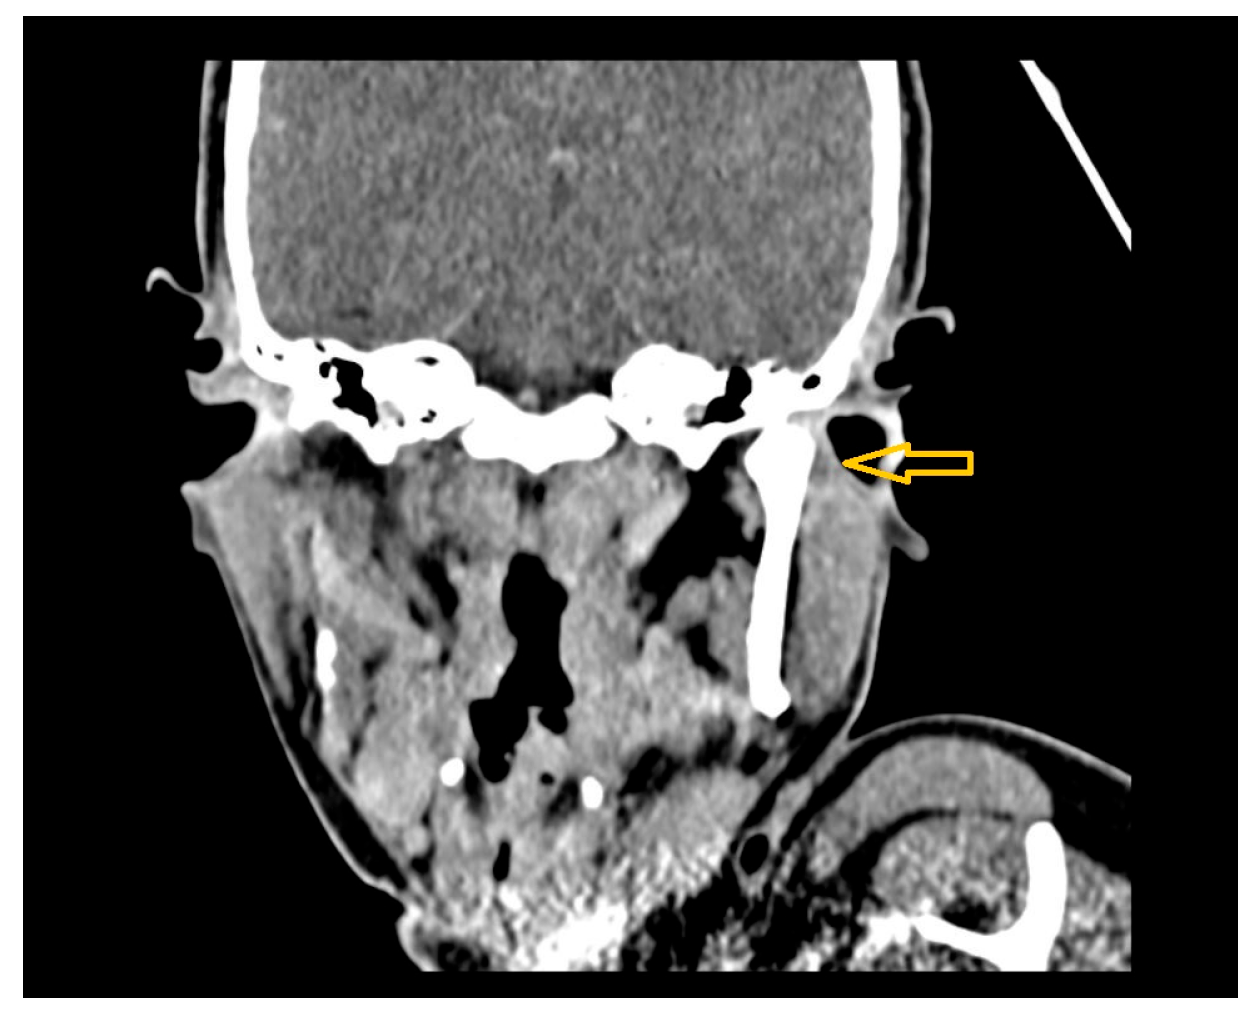

- Case 4

- Case 5